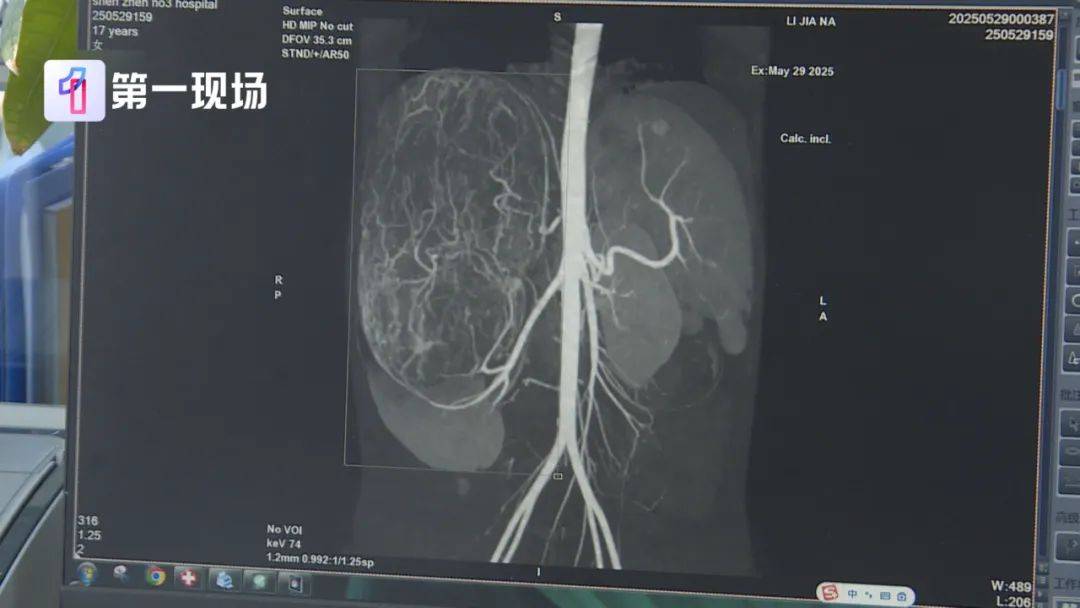

婷婷的肚子裡竟然長了一個巨大的腫瘤

直徑長達27公分

據深圳市第三人民醫院腎移植二科主任說明:腫瘤已經到了肚臍的下緣,就是後腹直肌外側,這種情況需安全地把腫瘤切除,不要把腫瘤搞破,是我們首先要考慮的問題。

切除的腫瘤將近2.5公斤重

直徑達27公分